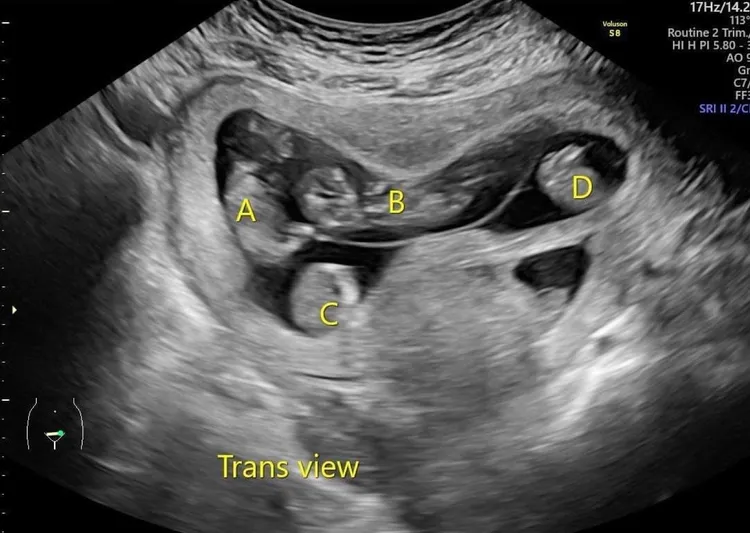

由於4胞胎發生早產與母體併發症的風險太高,蕭勝文建議郭小姐減少1胎,經超音波精準定位再以射頻燒灼(RFA)阻斷胎兒的血流供給,進而達成減胎目的,這是也是目前國際趨勢。